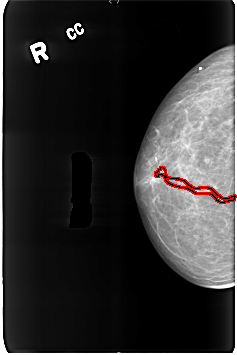

B_3164_1.RIGHT_CC

FILE: B_3164_1.RIGHT_CC.OVERLAY

TOTAL_ABNORMALITIES 1

ABNORMALITY 1

LESION_TYPE CALCIFICATION TYPE VASCULAR DISTRIBUTION N/A

ASSESSMENT 2

SUBTLETY 4

PATHOLOGY BENIGN_WITHOUT_CALLBACK

TOTAL_OUTLINES 1

BOUNDARY